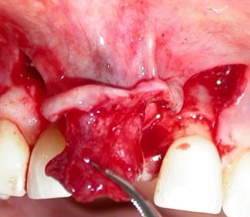

La mise en place d'un implant au niveau d'une crête osseuse se situant dans le secteur antérieur doit tenir compte de 2 facteurs essentiels. Le premier : pour que la papille inter-dentaire se régénère, il faut que la plate-forme de l'implant se trouve à une distance d'environ 3mm de la jonction amélo-cémentaire des dents adjacentes. Le deuxième : lorsque un implant est mis dans une crête, il doit être recouvert en vestibulaire et en palatin d'une couche osseuse d'au moins 2 mm.